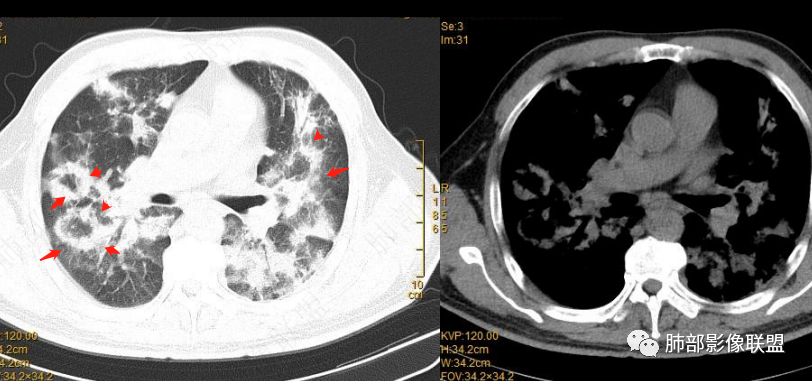

2022.2.17CT显示两肺中内带多发结节影、斑片影、条索影,部分病灶侧向融合与胸膜平行。部分病灶沿着支气管血管束分布、其内支气管稍扩张。部分病灶呈反晕征。大部分病灶边界显示清晰,部分病灶周围可见边界不清的GGO。2022.4.12CT显示两肺中内带多发结节影、条索状、条带状高密度影,边界收缩平直凹陷,大部分病灶沿着支气管血管束分布,亦有位于胸膜下侧向融合与胸膜平行的病灶。总体与第一次CT对比两肺病灶明显吸收。